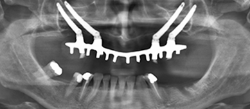

Imagen en alta resolución. Este enlace se abrirá mediante lightbox, puede haber un cambio de contextoPara estos casos tan severos, señala Manuel Chamorro, se han desarrollado 2 técnicas diferentes: "Por un lado los implantes cigomáticos que se trata de unos implantes más largos que los habituales que se insertan en el hueso cigomático (hueso del pómulo) y se pueden combinar con implantes convencionales. Pueden colocarse 2 cigomáticos en combinación o 4 implantes cigomáticos que pueden ser suficientes para colocar una rehabilitación dental completa y fija".

Y por otro, según el experto, recientemente se ha introducido y desarrollado los implantes subperiósticos a medida. "En este caso se trata de una estructura, diseñada a medida, que abraza, se adapta y se fija íntimamente al hueso por su cara externa. Por tanto, la estructura no entra en el hueso, sino que se apoya en su superficie. Esta estructura se diseña a medida de cada maxilar previa realización de un TAC 3-D. De la estructura emergen unos cilindros que salen a través de la encía y fijan la prótesis dental".

Para el Dr. Manuel Chamorro, las ventajas de esta técnica son evidentes: permite colocar prótesis dentales fijas en maxilares muy atróficos de una manera sencilla. La prótesis dental se coloca el mismo día, ya que no hay que esperar un tiempo de osteointegración. No se invade el seno maxilar. Por lo que puede realizarse sin problemas incluso en pacientes que han sufrido sinusitis.

"Nosotros realizamos en Olympia los implantes cigomáticos y los subperiósticos bajo anestesia general en régimen ambulatorio. El paciente es dado de alta una o dos horas después de la colocación de los implantes y la prótesis, concluye el Dr. Manuel Chamorro.